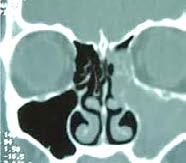

lo largo del desarrollo craneodento facial, tenemos la obstrucción de las vías aéreas superiores, que afectan y modifican su pleno crecimiento ade cuado. Entre estas afecciones están principalmente la sinusitis, hipertro fia de cornetes y amigdalitis crónica (Figura 25-27).

25